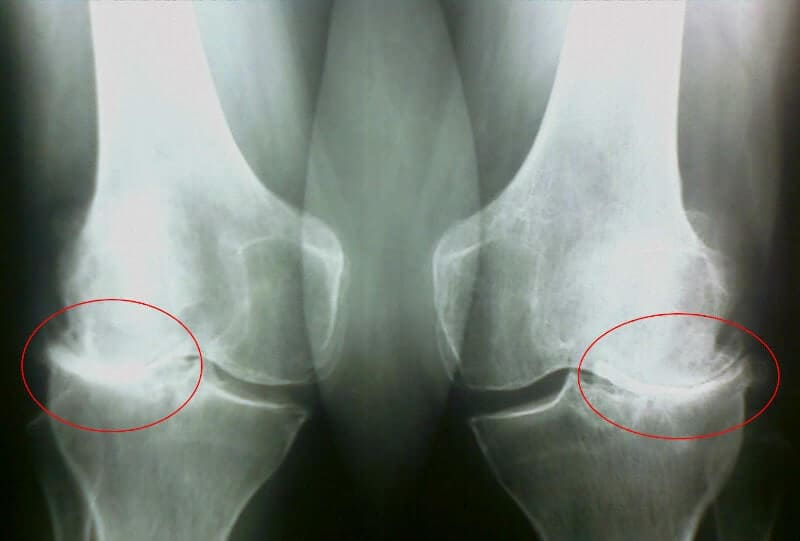

35 кун: таҳлил топширдим ва рентген қилдирдим. Артроздан ҳеч қандай из ҳам қолмаган! Бўғимлар тўқималари ҳудди 30 ёшдаги йигитдек. Шифокор ўтган сафарги рентгенда камчилик ёки тушунмовчилик бўлгани сабабли, артроз ташхиси хато бўлган бўлиши мумкинлигини айтди.